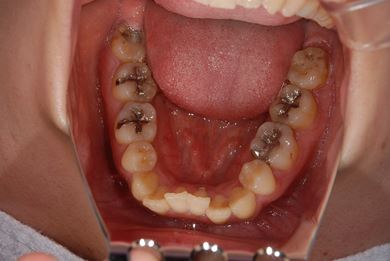

治療前

• 治療前